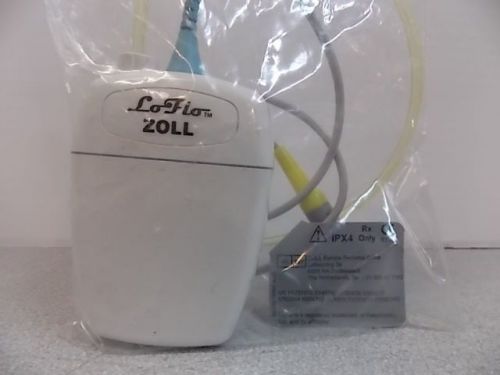

Zoll 8000-0365 M Series Sidestream LoFlo CO2 Module